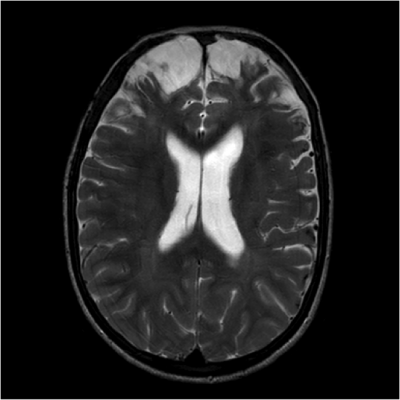

Much of previous research on the subject has focused on either the brain’s neuron-containing gray matter or the fiber tracts in the white matter. For this new study, researchers combined two MRI techniques — T1-weighted MRI and diffusion-tensor imaging (DTI) derived from diffusion weighted MRI — to look at both types of brain tissue.

“DTI is specific to the white matter part of the brain and T1-weighted images are sensitive to the gray matter,” said study lead author Virendra Mishra, Ph.D., from the Cleveland Clinic Lou Ruvo Center for Brain Health in Las Vegas. “By combining these approaches, we hoped to find imaging biomarkers on MRI that could be used to predict whether or not fighters will become impaired.”

The study revealed a set of seven imaging predictors, including regions of gray matter and white matter, which were associated with cognitive function in fighters. For instance, T1-weighted volumetric measurements of the left thalamus, a mass of gray matter in the middle of the brain that acts as a relay center connecting a multitude of brain regions, helped distinguish cognitively impaired and non-impaired fighters. Fractional anisotropy values, a measure of white matter integrity, along two different white matter tracts were also identified as possible predictors of cognitive impairment. The researchers concluded that this set of seven brain regions comprising of both gray and white matter may become imaging biomarkers of cognitive impairment in fighters.

“We found lower gray matter volume and thickness measures along with lower white matter tract integrity at baseline measurements that declined over time in those with ongoing trauma, and only by looking at both were we able to predict which fighters would be cognitively impaired,” Mishra said. “The combined observation of both gray and white matter as useful predictors of cognitive impairment is understandable because these two types of brain tissue work in tandem.”